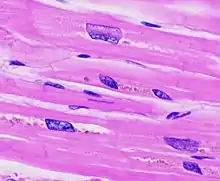

Concentric hypertrophy is characterized by an addition of sarcomeres (the contractile units of cardiac cells) in parallel. The result is an increase in thickness of the myocardium without a corresponding increase in ventricular size. This is maladaptive largely because there is not a corresponding proliferation of the vasculature supplying the myocardium, resulting in ischemic areas of the heart. Ultimately, this response can be compensatory for a duration, and allow for improved cardiac function in the face of stressors. However, this type of hypertrophy can result in a dilated ventricle which is unable to effectively pump blood, leading to heart failure.[3] When stressors that encourage this concentric hypertrophy are reduced or eliminated (either surgically corrected in the case of cardiac defects, or hypertension is reduced from diet and exercise) it is possible for the heart to undergo 'reverse remodeling', returning to a somewhat more 'normal' state instead of progressing to a dilated, pathologic phenotype.

Eccentric hypertrophy is generally regarded as healthy, or physiologic hypertrophy and is often termed "athlete's heart." It is the normal response to healthy exercise or pregnancy,[4] which results in an increase in the heart's muscle mass and pumping ability. It is a response to 'volume-overload', either as a result of increased blood return to the heart during exercise, or a response to an actual increase in absolute blood volume as in pregnancy. This increase in pumping ability is the result of the addition of sarcomeres in series, which enables the heart to contract with greater force.[5] This is explained by the Frank Starling mechanism, which describes the sarcomere's ability to contract with greater force as more of the elements of its contractile units become engaged. This response can be dramatic; in trained athletes have hearts that have left ventricular mass up to 60% greater than untrained subjects. Rowers, cyclists, and cross-country skiers tend to have the largest hearts, with an average left ventricular wall thickness of 1.3 centimeters, compared to 1.1 centimeters in average adults. Though eccentric hypertrophy is termed 'athlete's heart' it is typically only found in individuals who are aerobically conditioned. For example, weight lifters tend to undergo remodeling which more closely resembles concentric hypertrophy, as the heart does not experience a volume-overload, but instead responds to transient pressure overload as a consequence of increased vascular resistance from pressures exerted on arteries by sustained muscular contraction.